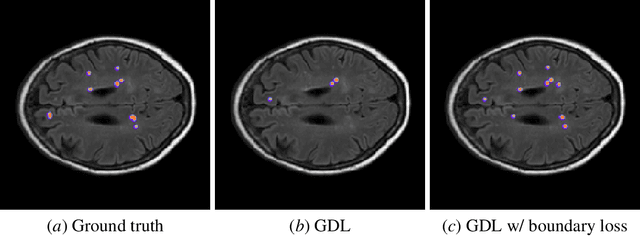

Abstract:Widely used loss functions for convolutional neural network (CNN) segmentation, e.g., Dice or cross-entropy, are based on integrals (summations) over the segmentation regions. Unfortunately, it is quite common in medical image analysis to have highly unbalanced segmentations, where standard losses contain regional terms with values that differ considerably --typically of several orders of magnitude-- across segmentation classes, which may affect training performance and stability. The purpose of this study is to build a boundary loss, which takes the form of a distance metric on the space of contours, not regions. We argue that a boundary loss can mitigate the difficulties of regional losses in the context of highly unbalanced segmentation problems because it uses integrals over the boundary between regions instead of unbalanced integrals over regions. Furthermore, a boundary loss provides information that is complementary to regional losses. Unfortunately, it is not straightforward to represent the boundary points corresponding to the regional softmax outputs of a CNN. Our boundary loss is inspired by discrete (graph-based) optimization techniques for computing gradient flows of curve evolution. Following an integral approach for computing boundary variations, we express a non-symmetric L2 distance on the space of shapes as a regional integral, which avoids completely local differential computations involving contour points. Our boundary loss is the sum of linear functions of the regional softmax probability outputs of the network. Therefore, it can easily be combined with standard regional losses and implemented with any existing deep network architecture for N-D segmentation. Our boundary loss has been validated on two benchmark datasets corresponding to difficult, highly unbalanced segmentation problems: the ischemic stroke lesion (ISLES) and white matter hyperintensities (WMH).